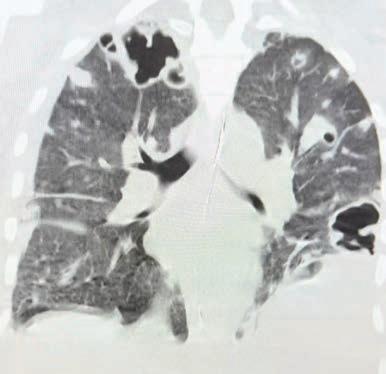

To coincide with the commencement of the National Lung Cancer Screening Program, ChestRad is bringing their sub-specialist service to Mandurah

ChestRad are specialists in Cardiac CT, Chest CT and Lung Cancer Screening

Cardiologists – Dr Edmund Brice, A/Prof Abdul Ihdayhid, A/Prof Chris Judkins, Dr Sam Tayeb, Dr Justin Teng and Dr Tashi Zhaxiduojie

Cardiothoracic radiologists – Dr Conor Murray and Dr Shriv Srigandan

ChestRad's rooms are at the Mandurah Specialist Centre on Minilya Parkway, Greenfields (near the Peel Health Campus) All rebatable Mandurah services BULK BILLED! www.chestrad.com.au